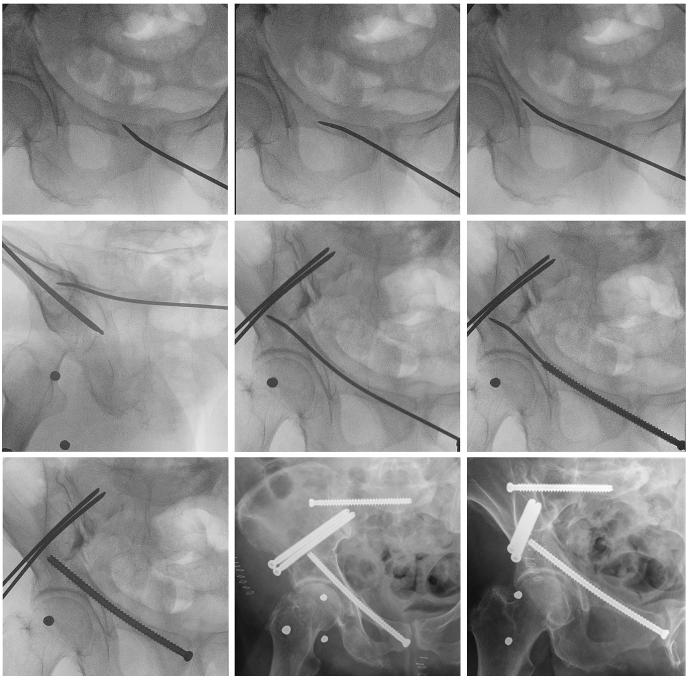

Zielsetzung und Fragestellung: Die transpubische Schraubenosteosynthese ist eine etablierte, minimalinvasive Möglichkeit für die Behandlung von Frakturen des oberen Schambeinastes. Allerdings findet sich in bis zu 38% der Patienten ein zu enger oder kurvierter transpubischer Korridor, sodass das Einbringen der Schraube in diesen Fällen kompliziert oder sogar frustran sein kann. Die hier präsentierte, modifizierte Technik für das Einbringen einer transpubischen Schauben über einen gebogenen Führungsdraht, der in einer ESIN-ähnlichen Methode eingebracht wird (Abbildung 1 [Abb. 1]), kann dieses Problem lösen. Das Ziel war die Überprüfung der Nicht-Unterlegenheit der modifizierten Technik gegenüber der klassischen Technik in einer Pilotstudie.

Abbildung 1: Intraoperative Bildsequenz der modifizierten Technik mit gebogenem Führungsdraht in ESIN-ähnlicher Methode für das Einbringen einer transpubischen Schraube sowie entsprechende, postoperative Röntgenbilder.